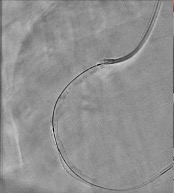

Percutaneous coronary intervention was initiated. A Xience Alpine 3.0 x 38mm drug-eluting stent (DES) was positioned at the mid to distal RCA and deployed at 16 atm and post-dilated using the same stent balloon inflated at 18 atm. Another Evermine 3.5 x 48mm drug-eluting stent (DES) was positioned at the proximal RCA and deployed at 18 atm and post-dilated using the same stent balloon inflated at 18 atm. Further dilation of the distal RCA was done using a Mini Trek 2.0 x 15mm balloon and inflated at 12 atm. However, j ust a few minutes after placing the stent. There was noted recurrence of the ST elevation on the cardiac monitor. A second look angiogram was immediately performed to check the patency of the stents. Immediately, manual distal displacement using the same stent balloon was done to displace the thrombus. Repeat angiogram showed TIMI II flow on the right coronary artery and resolution of the ST segment elevation.